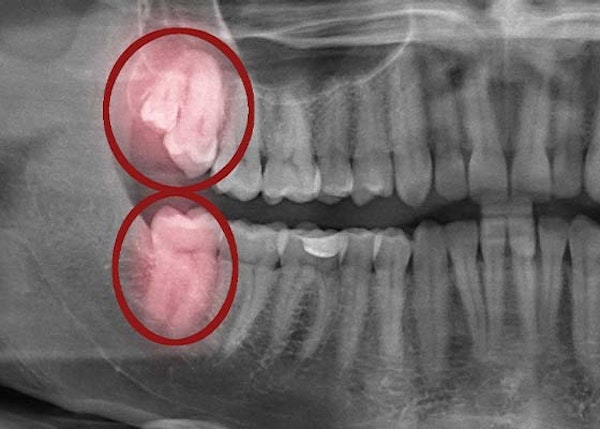

Your wisdom teeth are the backmost teeth on each dental arch. These molars emerge last, typically right before or around adulthood. While some wisdom teeth erupt without a problem, their emergence can sometimes cause infection and tooth misalignment when a dental arch doesn't have enough space to accommodate them.

Each type of tooth has its own specific function, except for wisdom teeth. When they erupt incorrectly, these teeth can actually harm your oral health by becoming partially stuck in the gums and causing an infection.

How Emerging Wisdom Teeth Change Your Mouth